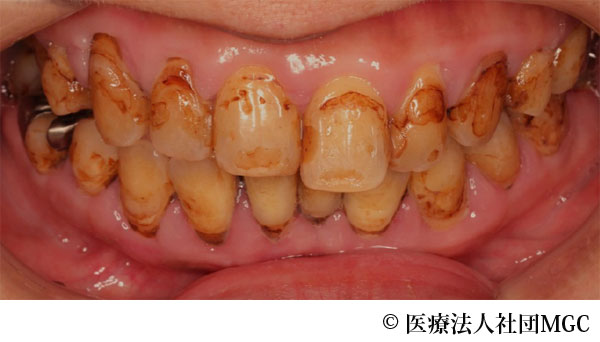

【症例4】上下All-on-4(オールオンフォー)

- 治療前

- 治療後

- 治療名

- 上下All-on-4(オールオンフォー)

- 費用

- 5,888,300円(税込)

- 期間

- 5ヵ月

治療内容

患者様の症状

歯の汚れが気になるのと、奥歯で噛めないとお困りでご来院されました。

治療法

ご相談の結果、患者様の生活の質(QOL)を向上させ、しっかり噛め、審美的にも重視した、上下All-on-4(オールオンフォー)を行いました。

治療結果

機能性、審美性ともに改善し、満足していただけました。

※治療結果は患者様によって個人差があります。

治療を行う上での注意点(リスク・副作用)

インプラント周囲炎の可能性、まれに歯が欠ける可能性があります。